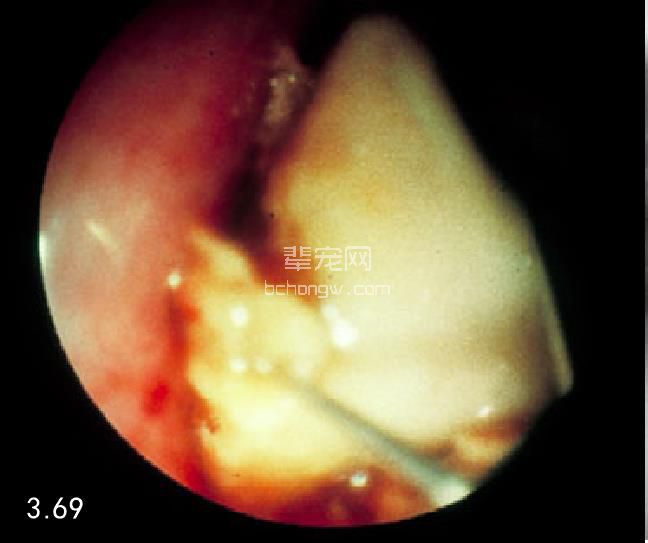

食管异物 胸腔X线片(图3.67)或内镜(图3.68)都可以确诊。有些食管异物可以用内镜取出或捅入胃内 (图3.69)。这项技术为操作者提供了良好的视野,同时还可以对黏膜损伤的程度进行评估(图3.70)。如果这 项操作能够成功,最大的好处就是可以不用实施手术。

图3.69 用镊子夹住骨头并将其从这只5岁大的犬的食道内取出。